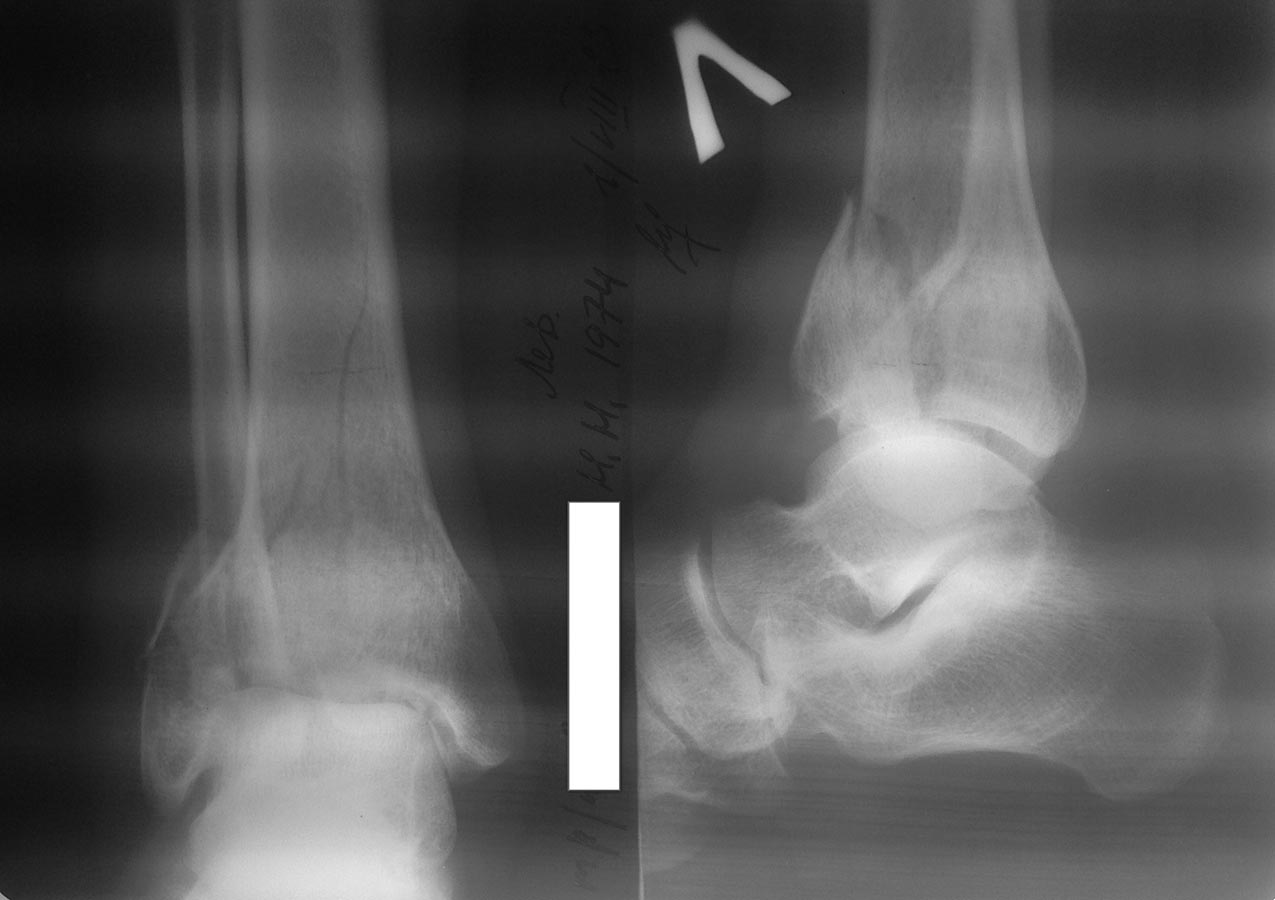

Перелом пилона

Больной 1974 года рождения, мужчина. Обстоятельство травмы: падение с высоты 2-ух метров. В настоящее время наложены гипсовые лонгеты на обе нижние конечности, отек умеренный, единичные фликтены.Чувствительность и движения в пальцах стоп в норме.Из вредных привычек - курение (более 20 лет)...

Имеется внутрисуставной перелом тибии со смещением + перелом наружной лодыжки (чрезсиндесмозное повреждение) с вальгусным (скорее всего) отклонением стопы. По всем понятиям просится остеосинтез, а какой и чем это решать Вам.

При переломах пилона всегда желательно делать КТ.

К сожаленью, рентгенологическая картина часто не соответствует реальной. Планирование операции в данном случае без КТ-исследования равнозначно принципу: "сделаем разрез, а там разберемся". Время (пока не появятся морщинки) есть - дообследуйте больного. Тогда гораздо проще будет выбрать операционный доступ и импланты.

По поводу тактики оперативного лечения, действительно стоит сделать КТ сустава (желательно с 3D реконструкцией), по результатам - большеберцовую кость: или пластиной 1/3 трубки и винтами, или же антелатеральной пластиной, а малоберцовую - пластиной 1/3 трубки.